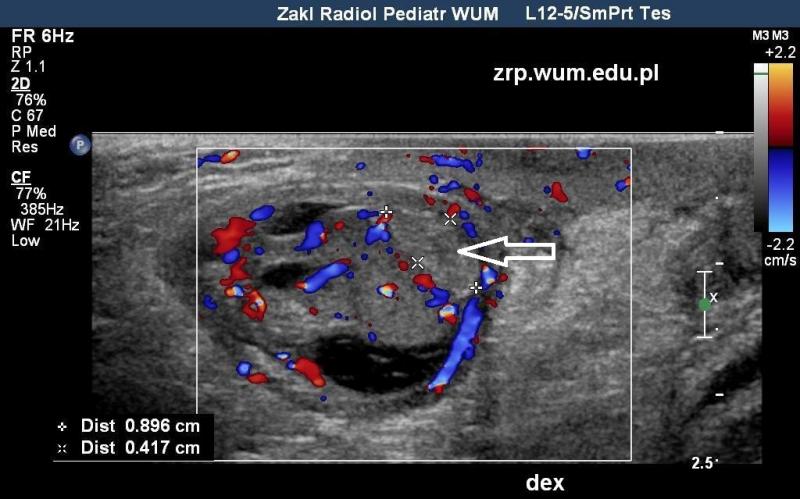

Przypadek 50: 2-miesięczny chłopiec zgłosił się na badanie usg z podejrzeniem przepukliny pachwinowej lewostronnej.

Rozpoznanie: W badaniu usg - uwidoczniono przepuklinę pachwinowę lewostronną - w kanale pachwinowym i w mosznie po stronie lewej widoczne pętle jelitowe (białe strzałki), z zachowaną perystaltyką. Oba jądra widoczne w mosznie, o prawidłowej strukturze i wielkości (czerwona strzałka - jądro prawe, pomarańczowa strzałka - jądro lewe, widoczne poniżej pętli jelitowych).